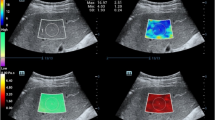

The methodology employed for the proteomics analysis is outlined in Fig. 1A. Quantitative proteomics analysis resulted in the identification of 7,491 proteins at 1% protein-level FDR. Principle component analysis showed striking separation of Wilson’s disease cases (n = 8) and control individuals (n = 8) indicating alterations at the proteomic-level in Wilson’s disease (Fig. 1B). Proteins differentially expressed in disease cases were identified using Student’s T test with multiple hypothesis correction. Overall, 588 proteins were over-expressed and 243 proteins were under-expressed with 1.5-fold difference (adjusted p value <0.05) in disease cases compared to controls (Fig. 1C). We did not identify the ATP7B protein in this study. We identified significant downregulation of COX17 (0.6-fold) which transports intracellular copper to cytochrome C oxidase complex. Despite COX17, we did not identify dysregulation of other copper chaperons such as ATOX1 and CCS. COMMD1, a protein involved in copper ion homeostasis, also remained unchanged in Wilson’s disease cases compared to control individuals. In order to understand the adaptive responses of liver cells upon copper accumulation, we performed functional characterization of the differentially expressed proteins using gene ontology enrichment analysis. Overexpressed proteins were significantly involved in several biological process such as interferon-γ-mediated signaling pathway, antigen processing and presentation, extracellular matrix reorganization, cell adhesion (Fig. 2A). Proteins involved in the immune response are shown as a protein-protein interaction network in Fig. 2B. Under-expressed proteins were significantly enriched in several metabolic processes such as oxidation-reduction processes, metabolism of xenobiotics, and steroid and lipid metabolic processes (Fig. 2C). The proteins involved in the redox reactions include CYP2C8, CYP2A6, CYP2C19, CYP3A4, HSD17B13, GFER, RDH16, VKORC1, SOD1 (Fig. 2D). Metallothionein-1M, was overexpressed by 1.7-fold in Wilson’s disease cases compared to control individuals (Fig. 3A). In addition to MT1M, MT1G was also overexpressed (1.5-fold; adj p value < 0.1) in WD cases (Fig. 3B). MS/MS spectrum of a representative peptide identified from MT1M is shown in Fig. 3C.

A Experimental strategy for quantitative proteomics analysis. B 2-dimensional principal component analysis of protein expression profiles across all the samples clearly segregating Wilson disease cases from control cases. C Volcano plot showing differentially expressed proteins in Wilson disease compared to controls (±1.5-fold; adj. p value < 0.05). Proteins overexpressed are highlighted in red and under-expressed proteins were highlighted in blue.